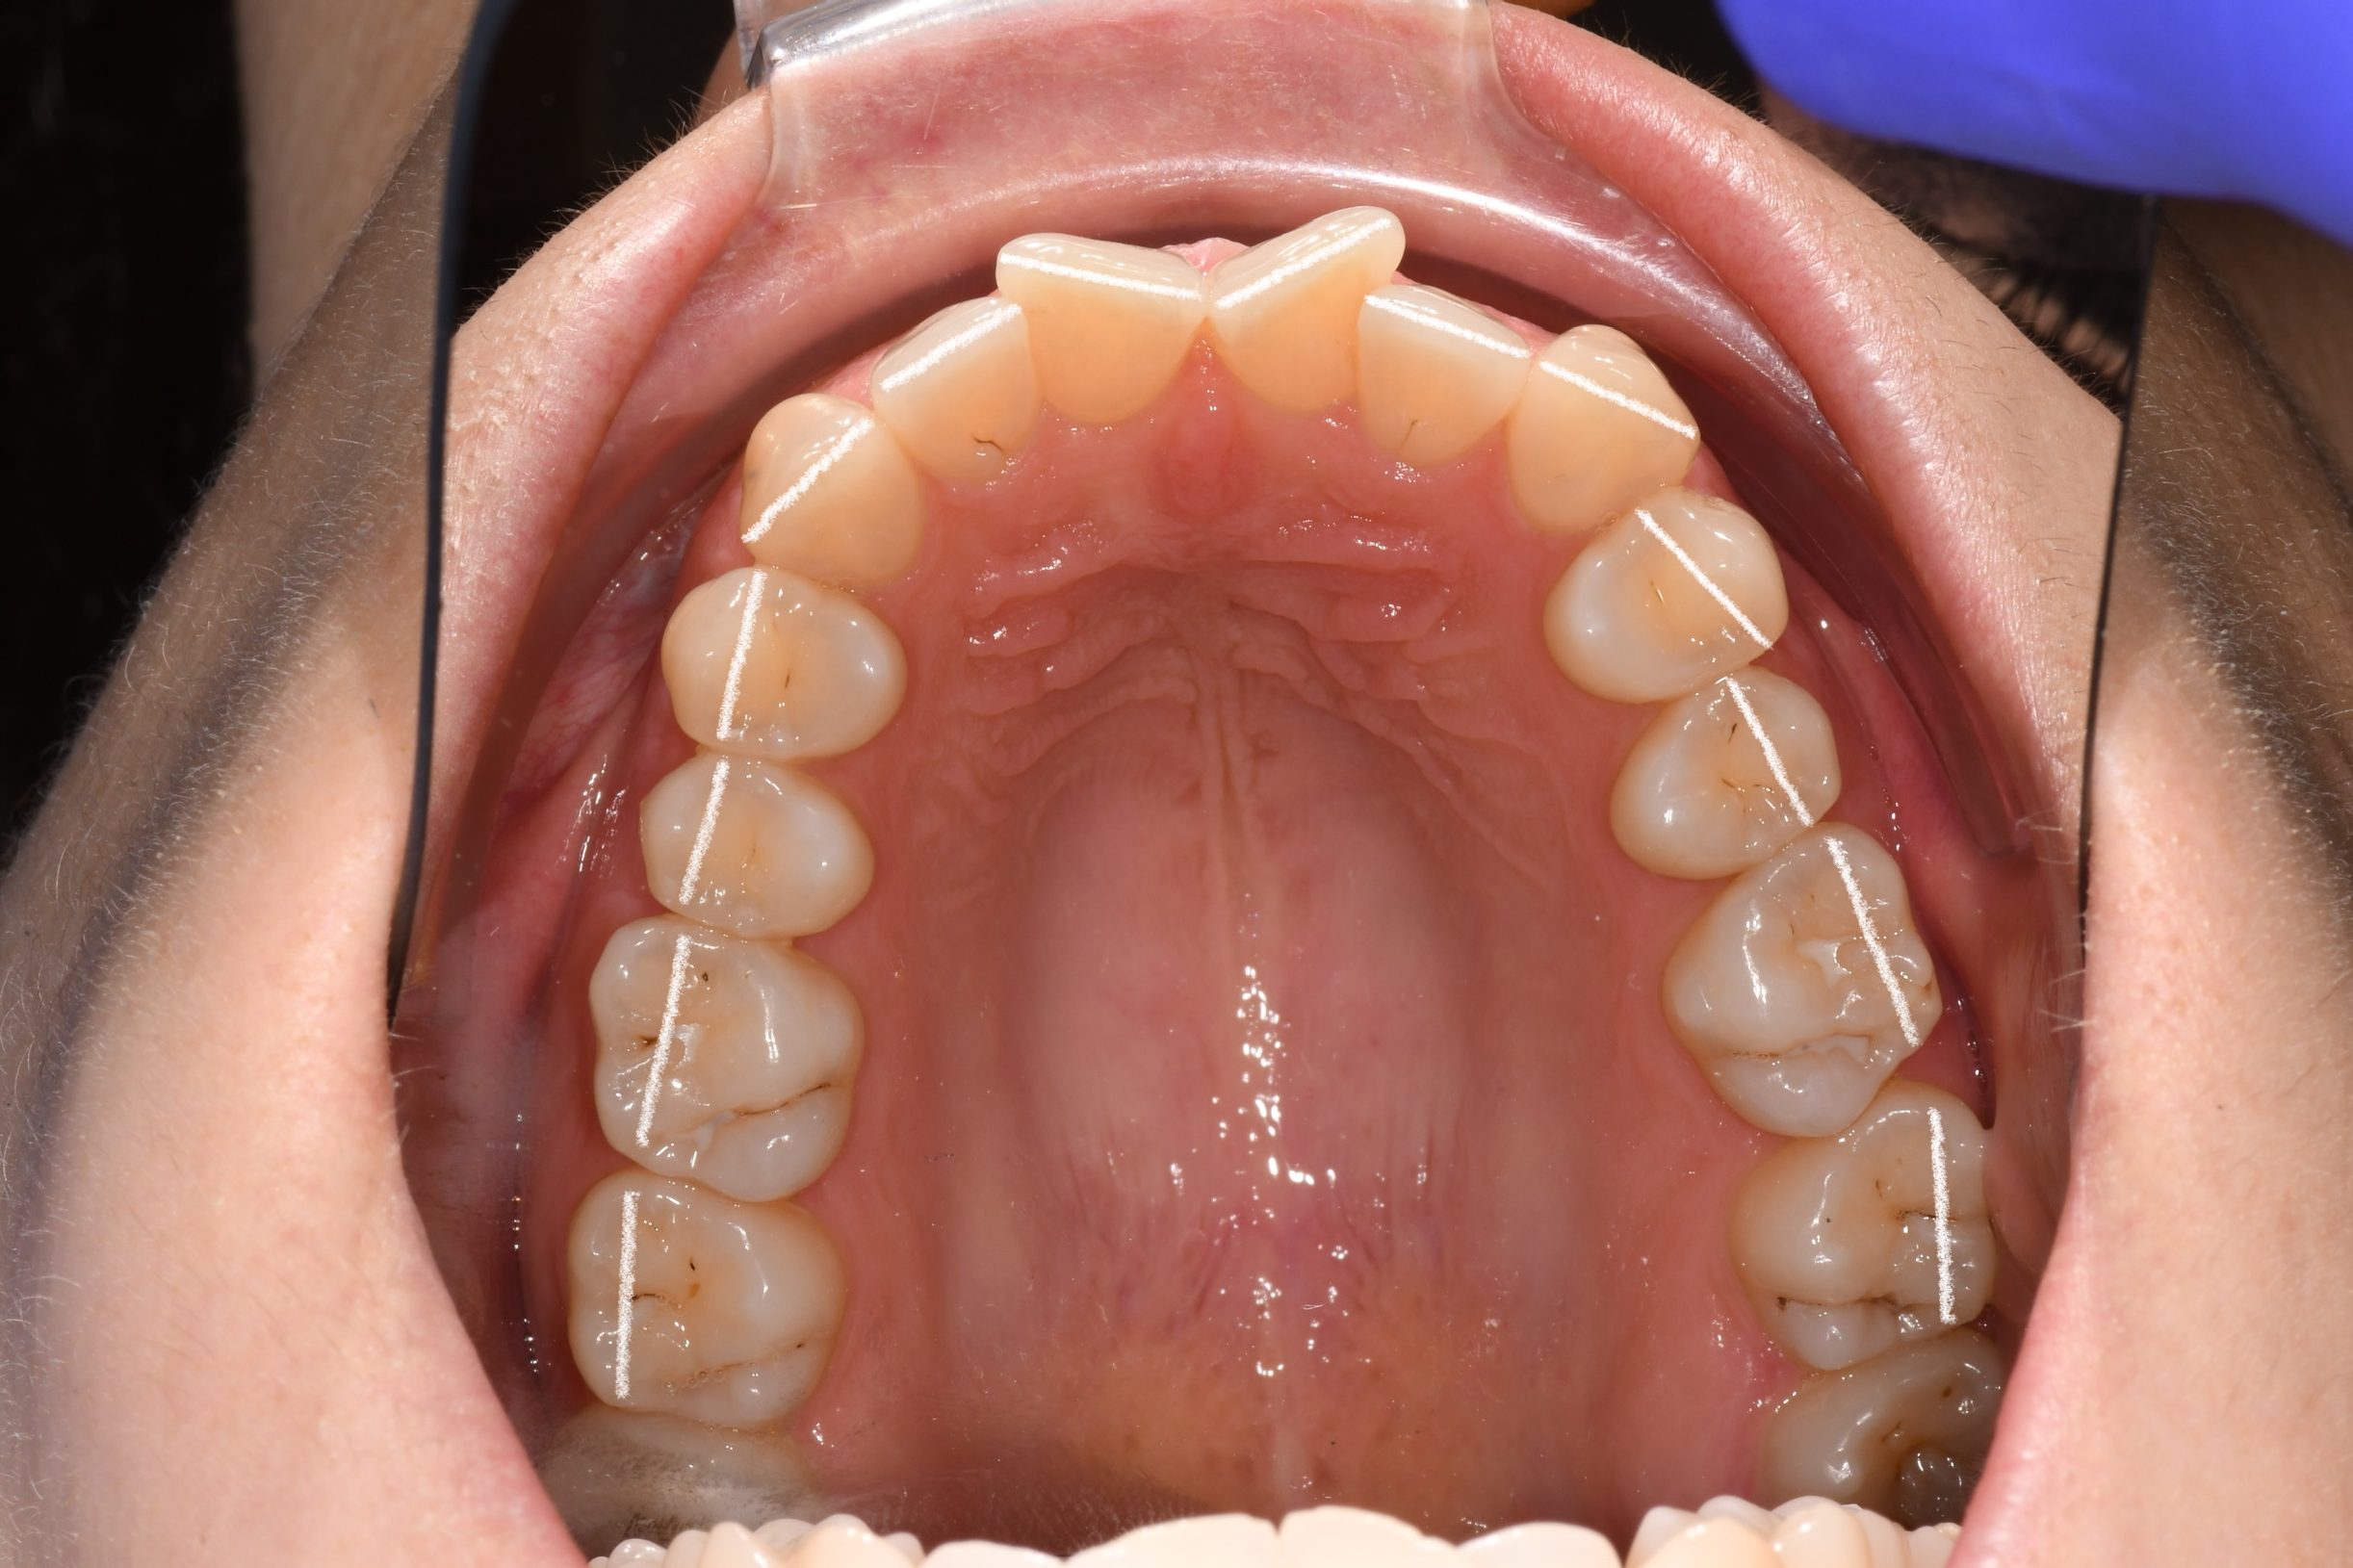

Az elmúlt évekből rengeteg szakmai referenciát tudnánk bemutatni, amelyek különböző fogszabályozási problémákat oldottak meg. Válogatva a több száz esetből, ezen az oldalon olyan képeket, információkat igyekeztünk bemutatni, amelyeknek a segítségével a jövőbeni pácienseinknek azt tudjuk üzenni: A Te fogsorod is lehet gyönyörű!

(Képeket a Pácienseink külön írásos beleegyezésével mutatjuk be!)